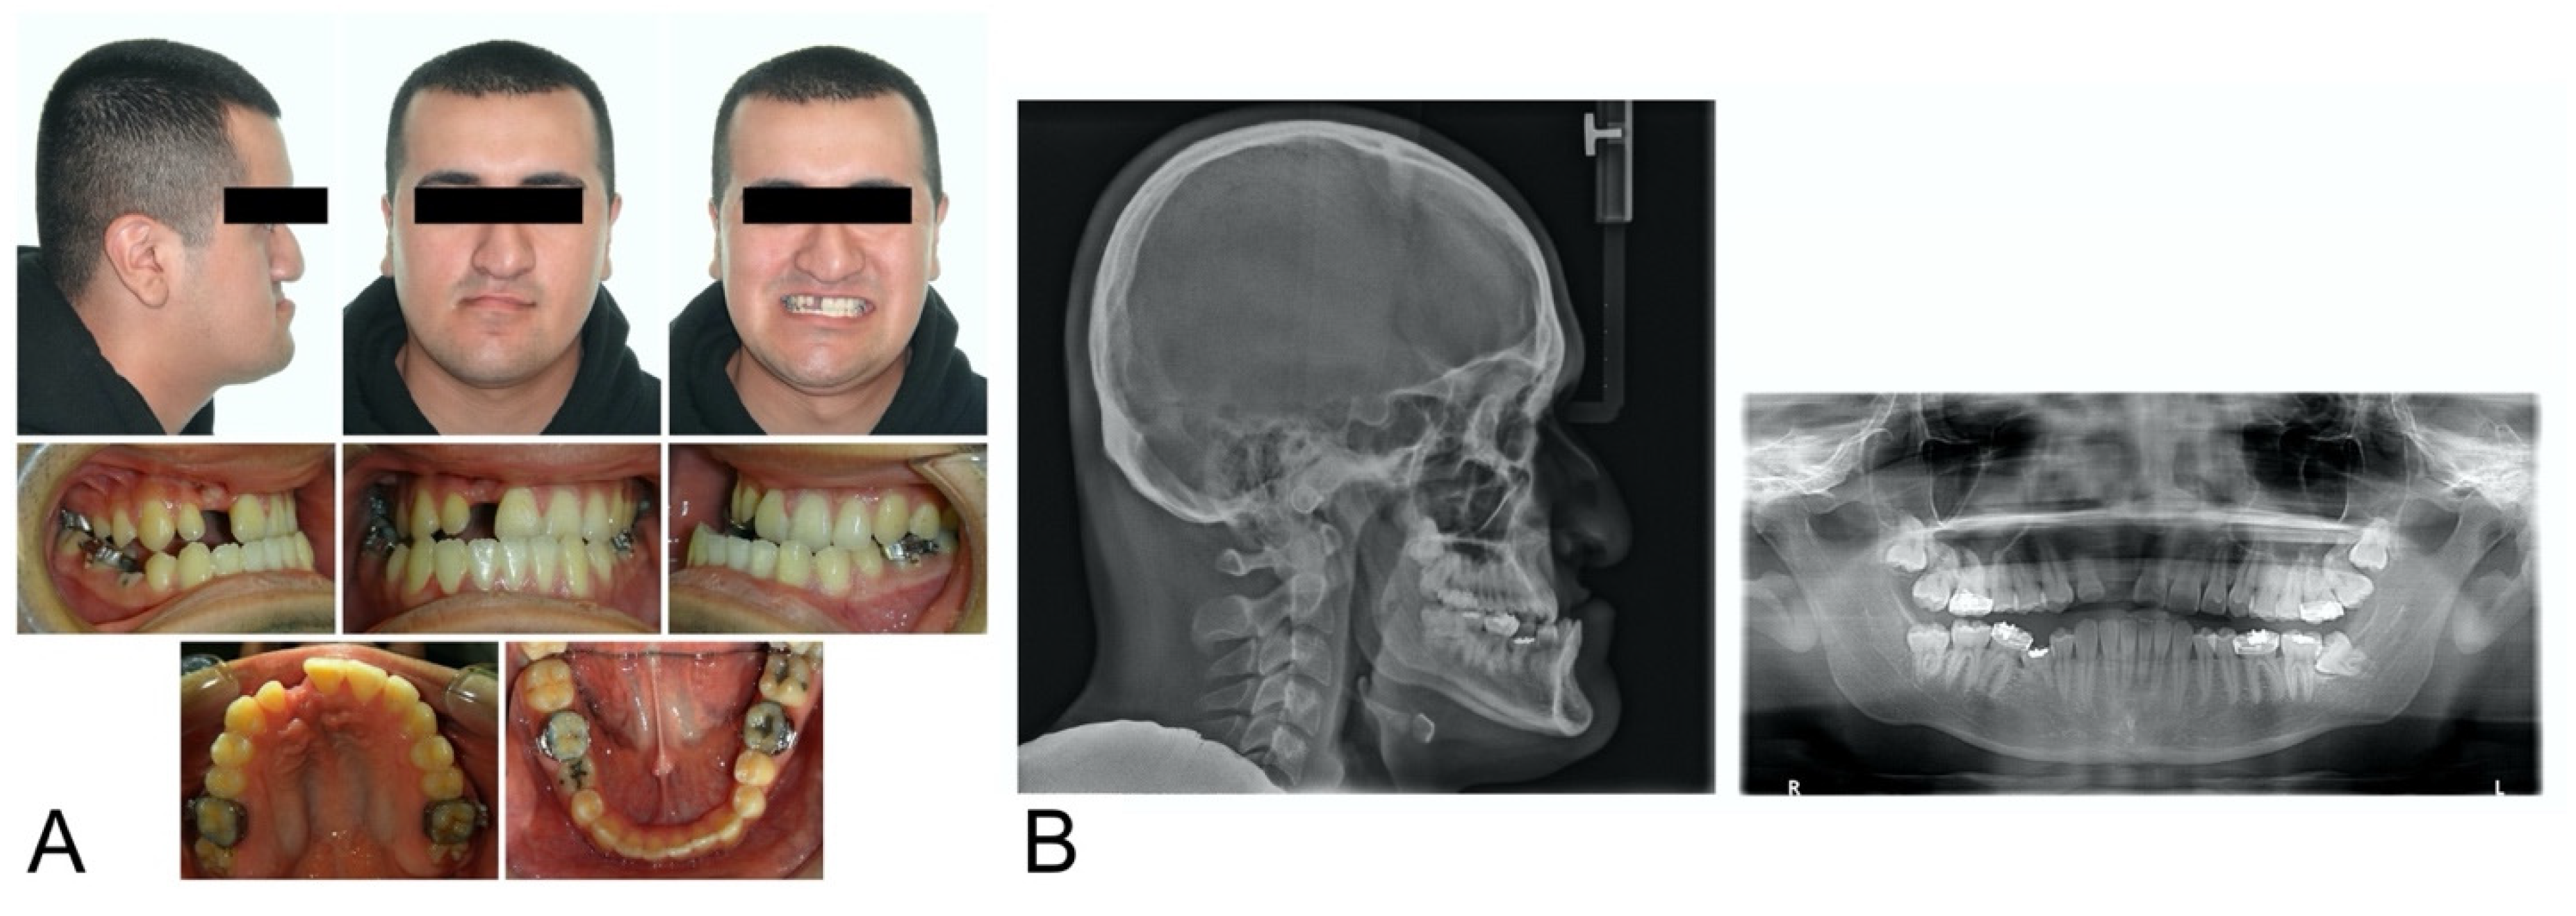

2. Case Description

| Measurement | Normal | Pretreatment |

|---|---|---|

| Skeletal | ||

| SNA (°) | 82.0 ± 3.5 | 78 |

| SNB (°) | 80.9 ±3.4 | 87.7 |

| ANB (°) | 1.6 ± 1.5 | −9.7 |

| A-Na Perpendicular (mm) | 1.1 ± 2.7 | 2.4 |

| Pog-Na Perpendicular (mm) | −0.3 ± 3.8 | 30.5 |

| Co-A (mm) | 99.8 ± 6.0 | 79.8 |

| Co-Gn (mm) | 134.3 ± 6.8 | 132.6 |

| Co-Gn—Co-A (mm) | 34.5 ± 4.0 | 52.8 |

| Wits (mm) | −1 ± 1.0 | −17.4 |

| SN-MP (°) | 33.0 ± 6.0 | 27.1 |

| Dental | ||

| U1-SN (°) | 103.1 ± 5.5 | 108.3 |

| L1-MP (°) | 95.0 ± 7.0 | 83.2 |

| Soft tissue | ||

| Upper lip to E-line (mm) | −4.0 ± 2.0 | −14.7 |

| Lower lip to E-line (mm) | −2.0 ± 2.0 | −5.3 |